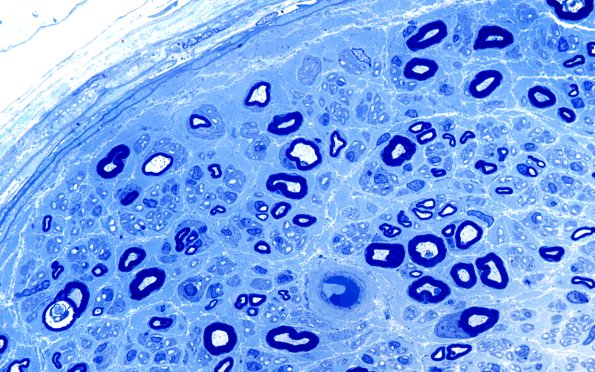

Washington University Experience | PERIPHERAL NEUROPATHY | 4 AXONAL DEGENERATION | 2 Plastic Sections | 27A2 Unmyelinated axons (Case 27) Plastic 100X 2

There are numerous unmyelinated axons in this biopsy which are present as singletons (a single unmyelinated axon per Schwann cell unit) not as part of Remak bundles. Singletons are a common finding in neuropathies generally in our experience.